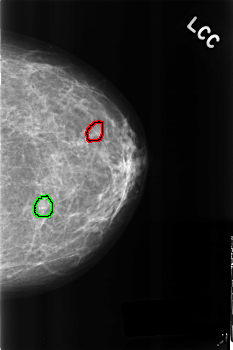

C_0271_1.LEFT_CC

LEFT_CC LINES 4544 PIXELS_PER_LINE 3024 BITS_PER_PIXEL 12 RESOLUTION 50 OVERLAY

FILE: C_0271_1.LEFT_CC.OVERLAY

TOTAL_ABNORMALITIES 2

ABNORMALITY 1

LESION_TYPE CALCIFICATION TYPE PUNCTATE DISTRIBUTION CLUSTERED

ASSESSMENT 4

SUBTLETY 5

PATHOLOGY BENIGN

TOTAL_OUTLINES 1

BOUNDARY

ABNORMALITY 2

ASSESSMENT 3

SUBTLETY 4